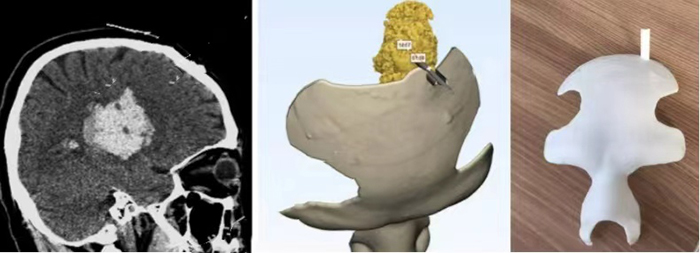

- 3d printed skull surgical guide

A patient in the neurosurgery department of a hospital in Shandong was diagnosed with a brain meningioma with a diameter of 1cm. It was an emergency. After consultation, resection was decided, and preoperative tumor positioning guide plate was made to accurately locate and remove the tumor in the patient's skull. With the help of CT scan data, the location of the meningioma was accurately located. By constructing a 3d brain model, the incision location was determined, and the surgical positioning guide plate matching the patient's skull was designed and printed in a short time, so as to assist the surgeons to successfully complete the resection of the left parietal sinus meningioma.